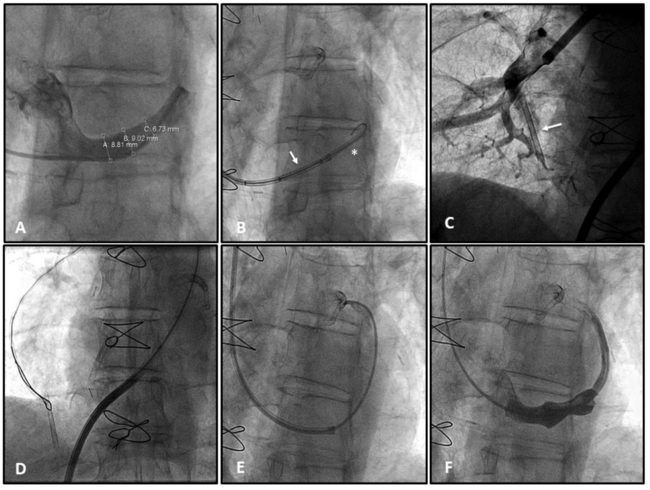

A multipurpose (MP) catheter was introduced in the CS via internal jugular vein access with a 9-Fr sheath and angiography confirmed suitable anatomy (Figure 1A). A 0.035˝ guidewire was advanced distally in the CS to deliver the guiding catheter and reducer device to the landing zone. However, during the guiding catheter retrieval, we observed the stent outside and distal to the balloon (Figure 1B). Although we attempted to maintain the wire inside the stent, during the retrieval of the balloon catheter, the unexpanded stent migrated to the pulmonary artery (Figure 1C).

An 11-Fr sheath was advanced to the pulmonary artery over a 0.035˝ guidewire through a femoral vein. The reducer was snared and extracted without complications (Figure 1D). A second reducer device was implanted using a mother-and-child technique, advancing the guiding catheter of the 9-Fr device through a 5-Fr multipurpose catheter (Figure 1E). After advancing the guiding catheter more distally to the landing zone, we retrieved the MP catheter and delivered the reducer with successful implantation (Figure 1F).